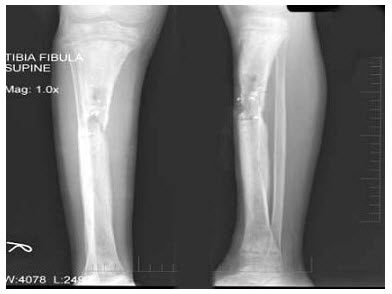

125、单项选择题

患者,男性,39岁,左小腿肿胀、疼痛1个月余,夜间加重。左胫腓骨正侧位片如下,最可能的诊断为()

A.成骨性转移瘤

B.骨肉瘤

C.软骨肉瘤

D.Ewing肉瘤

E.慢性硬化性骨髓炎

点击查看答案